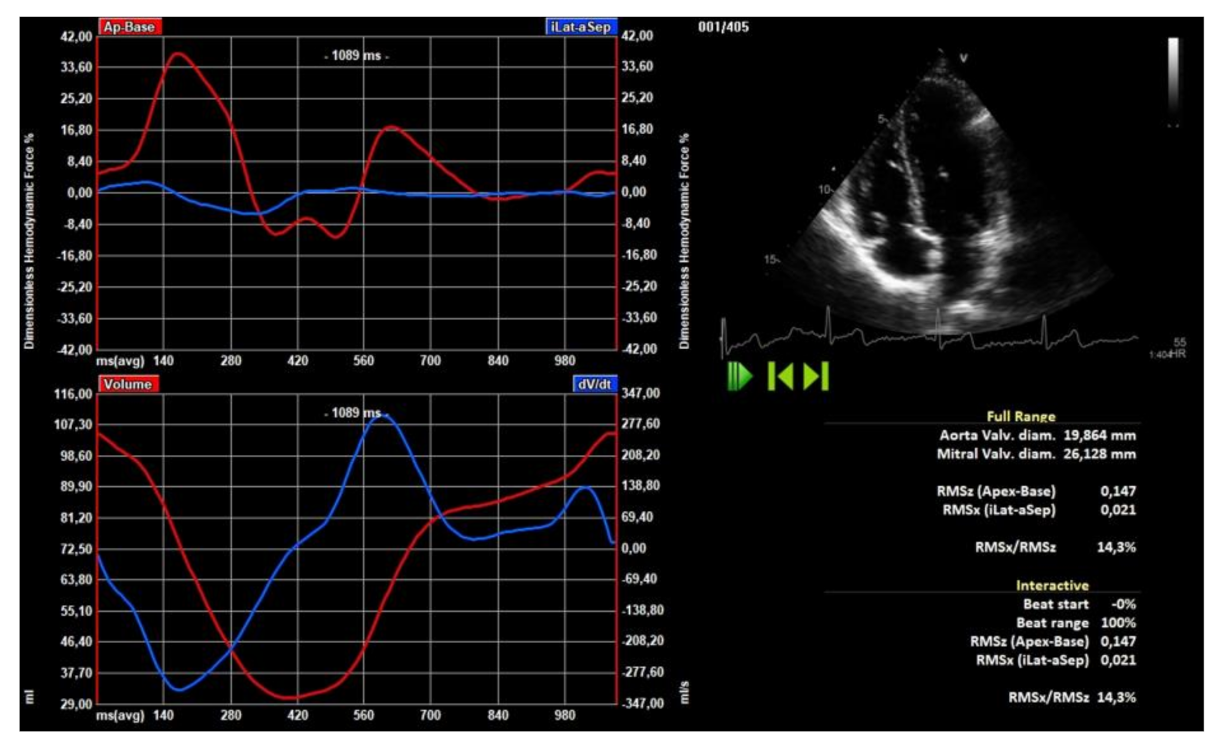

2.4. Hemodynamic Forces

3.5. LV Hemodynamic Forces

3.6. Clinical and Echocardiographic Correlates of LV Hemodynamic Force